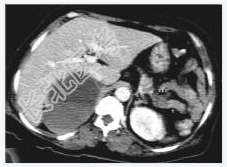

- [材料题] 女性,59岁,胸闷、头晕2天,呈持续性,伴呕吐,以进食后明显。发现“高血压”10年,“糖尿病”2年。体格检查:血压70~210/30~120mmHg。

- 简答题1、该病患诊断是什么?

- 简答题2、鉴别诊断有哪些?

- 简答题3、右肾上腺嗜铬细胞瘤囊变的定义是什么?

- 简答题4、右肾上腺嗜铬细胞瘤囊变的临床意义是什么?

- 简答题5、右肾上腺嗜铬细胞瘤囊变的诊断和治疗上需要注意哪些事项?